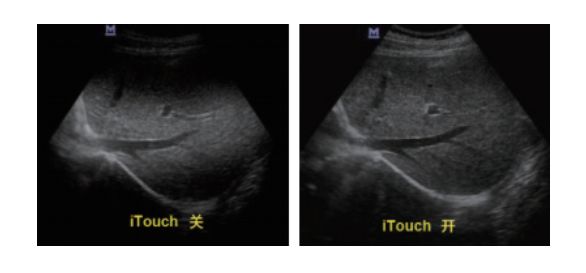

设备型号DP-50 全自动便携式超声诊断系统(迈瑞),该设备为DP 系列超声的较高级版本,具有iTouch 图像一键优化、 iBeam 复合成像、iClear 斑点噪声抑制、宽带频移谐波等技术。

iTouch图像一键优化: